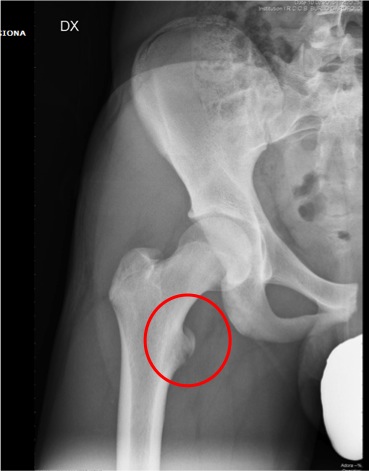

Dopo sette giorni per� Giona ritorna per persistenza del dolore e impossibilit� a sollevare l�arto inferiore; obiettivamente si nota una tumefazione del terzo prossimale del femore con dolore alla palpazione e alla mobilizzazione. Ripetiamo quindi la radiografia, che mette in evidenza un distacco, ma non di una spina iliaca, bens� del piccolo trocantere del femore! (Figure).

I distacchi apofisari sono fratture tipiche dell�et� evolutiva che si verificano quando l�apofisi immatura viene sollecitata da una contrazione muscolare improvvisa e intensa. La sede pi� frequente � il bacino con, in ordine di frequenza, la tuberosit� ischiatica, la spina iliaca antero-inferiore e antero-superiore, e il piccolo trocantere. La clinica � caratterizzata dall�insorgenza improvvisa di dolore inguinale durante l�attivit� sportiva.